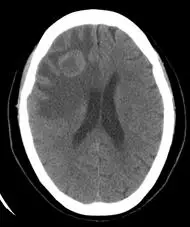

56 歲肺癌男性,最近兩天頭痛,肢體無力, CT 顯示右側腦部白質( white matter )一片低密度區域, 請問這低密度區域所指主要為何? 圖片

圖片為腦部非對比 CT(non-contrast CT brain)橫切面影像,顯示:

• 右側大腦半球:大片低密度(hypodense)區域,主要分布於白質(white matter),呈手指狀延伸(finger-like projection)模式,符合血管源性水腫特徵

• 灰質相對保留:低密度區域主要侷限於白質,皮質灰質(cortical grey matter)密度相對正常,此為血管源性水腫(vasogenic edema)的特徵性表現

• 佔位效應(mass effect):右側腦室受壓,中線結構可見輕度向左偏移

• 無高密度出血灶:未見明顯高密度(hyperdense)區域,排除急性出血性中風

• 腫瘤本體:在此非對比影像上腫瘤本體不明顯,需對比增強 CT 或 MRI 方能清楚顯示,但周圍廣大水腫區域強烈提示腦轉移伴隨腦水腫

此影像所見:大片白質低密度 + 無出血 + 有肺癌病史,強烈支持腦轉移瘤旁血管源性水腫(perit